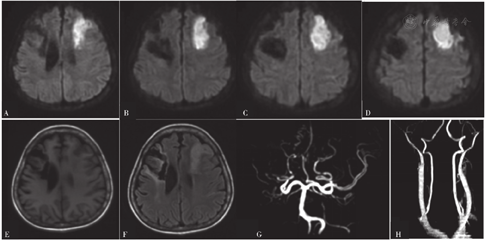

患者,女,29岁,因"左上肢麻木无力4 d,加重1 d"于2015-02-09首次入住滨州医学院附属医院。患者入院前4 d无明显诱因出现左上肢麻木无力,尚能持物,1 d前左上肢麻木较前加重,为求系统诊疗而就诊于滨州医学院附属医院,门诊以"肢体麻木无力、原因待查"收入院。查体:血压为165/84 mm Hg(1 mm Hg=0.133 kPa),心率为116次/min,意识清,言语流利,左侧鼻唇沟浅,左侧口角略低,伸舌左偏,左侧肢体肌力为4级,左上肢针刺痛觉减退,左侧共济运动欠稳准,左侧Babinski征(+),左侧Pessep征(+),美国国立卫生研究院卒中量表(NIHSS)评分为3分。颅脑磁共振成像(MRI)检查结果:右侧基底核、右侧放射冠、右侧半卵圆中心及右额叶区急性脑梗死灶。头颈部磁共振血管成像(MRA)检查结果:右侧颈内动脉颅内段、右侧大脑前动脉A1段、右侧大脑中动脉异常,考虑狭窄、闭塞;左侧颈内动脉终段管腔局限性明显狭窄(见图1)。经颅多普勒超声(TCD)检查结果:右侧大脑中动脉、大脑前动脉及颈内动脉严重狭窄或闭塞,左侧大脑中动脉近端、大脑前动脉或颈内动脉末端狭窄。甲状腺超声检查结果:甲状腺弥漫性增大,实质回声不均,血流丰富,流速增高,符合甲状腺功能亢进症表现。甲状腺功能指标:游离三碘甲状腺原氨酸为46.16 pmol/L(参考范围:2.80~7.10 pmol/L),游离甲状腺素>100 pmol/L(参考范围:12~22 pmol/L),促甲状腺激素为0.006 mU/L(参考范围:0.270~4.200 mU/L),抗甲状腺球蛋白抗体为1 651.0 U/ml(参考范围:0~1.5 U/ml),甲状腺过氧化物酶抗体为170.0 U/ml(参考范围0~34.0 U/ml)。心电图检查结果:窦性心动过速;中度ST段压低。

注:A~D为颅脑磁共振平扫+弥散加权成像(DWI),依次示右侧基底核、右侧放射冠、右侧半卵圆中心及右额叶区急性脑梗死灶;E为头颈部磁共振血管成像(MRA),示右侧颈内动脉颅内段、右侧大脑前动脉、右侧大脑中动脉异常(考虑狭窄、闭塞),左侧颈内动脉终段管腔局限性狭窄